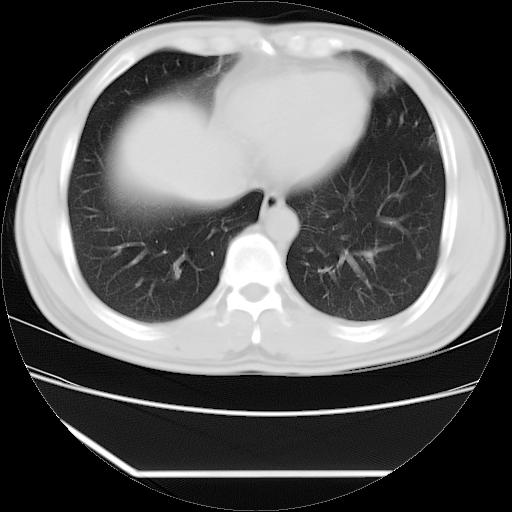

男,38岁,于2009年8月9日晚突发左侧胸痛,今x线提示左下肺阴影,为了明显确诊断,行ct检查,

血常规:嗜酸性细胞增高,单核细胞增高。

病灶发生在下叶,密度均匀,边缘模糊、毛糙,周围血管纹理增强扭曲改变,靠近胸膜处病灶胸膜反应明显。

支持考虑---球形肺炎。

左肺舌叶病变。主体病灶呈类圆形中心密度低,成液化趋势周边班片影分布

考虑肺脓肿

虽然实验室检查支持炎性病变,且病变内有坏死改变(中央呈大片状低密度影),但仍不能掉以轻心,鳞癌也可以有这种影像改变。